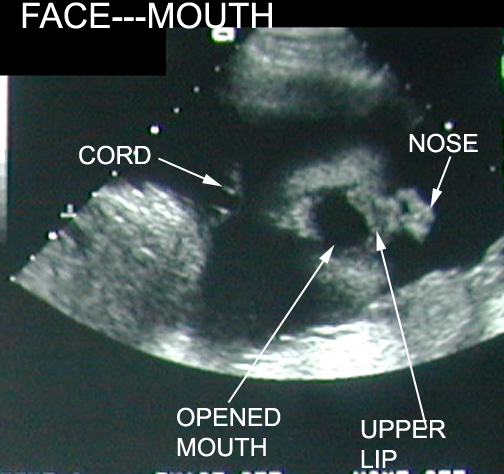

15 Weeks Intrauterine Pregnancy |

|

15 Weeks Intrauterine Pregnancy |

|